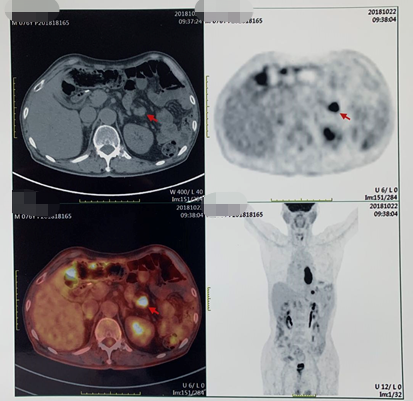

PET/CT(2018-10-22):食管中下段管壁增厚FDG代谢增高,吻合口下方肠壁FDG代谢增高灶;左上腹系膜区多发FDG代谢增高灶,考虑多发转移;后腹膜区及右侧髂血管旁多发小淋巴结FDG代谢轻度增高,倾向转移淋巴结。